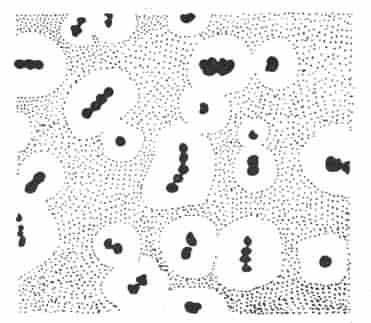

细菌的结构对细菌的生存、致病性和免疫性等均有一定作用。细菌的结构按分布部位大致可分为:表层结构,包括细胞壁、细胞膜、荚膜;内部结构包括细胞浆、核蛋白体、核质、质粒及芽胞等;外部附件,包括鞭毛和菌毛。习惯上又把一个细菌生存不可缺少的,或一般细菌通常具有的结构称为基本结构,而把某些细菌在一定条件下所形成的特有结构称为特殊结构(图2-2)。

图2-2 细菌的结构